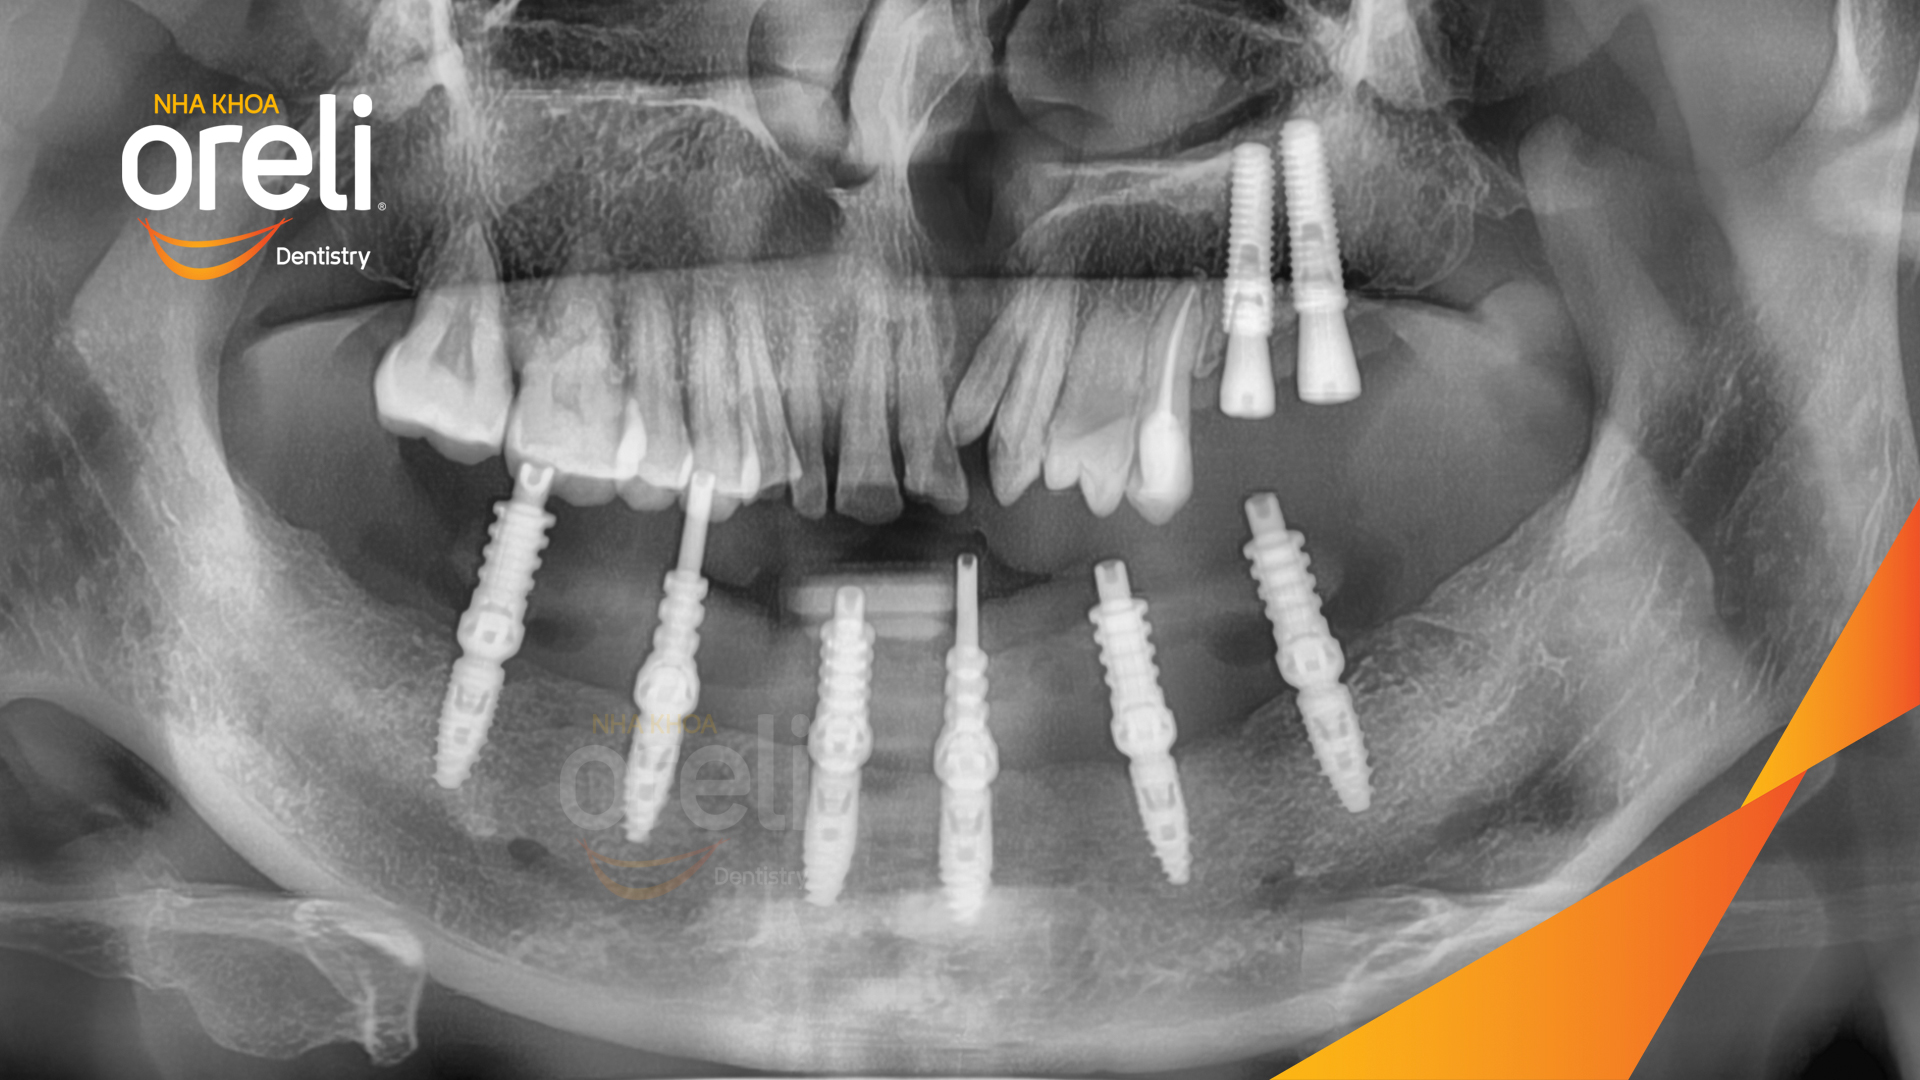

Tình trạng: Mất răng vùng răng sau hàm dưới, các răng trước lung lay mất khả năng hồi phục

Giải pháp: Nhổ răng trồng răng implant hàm dưới và hai răng hàm trên

Kết quả: Phục hồi vững chắc hàm dưới